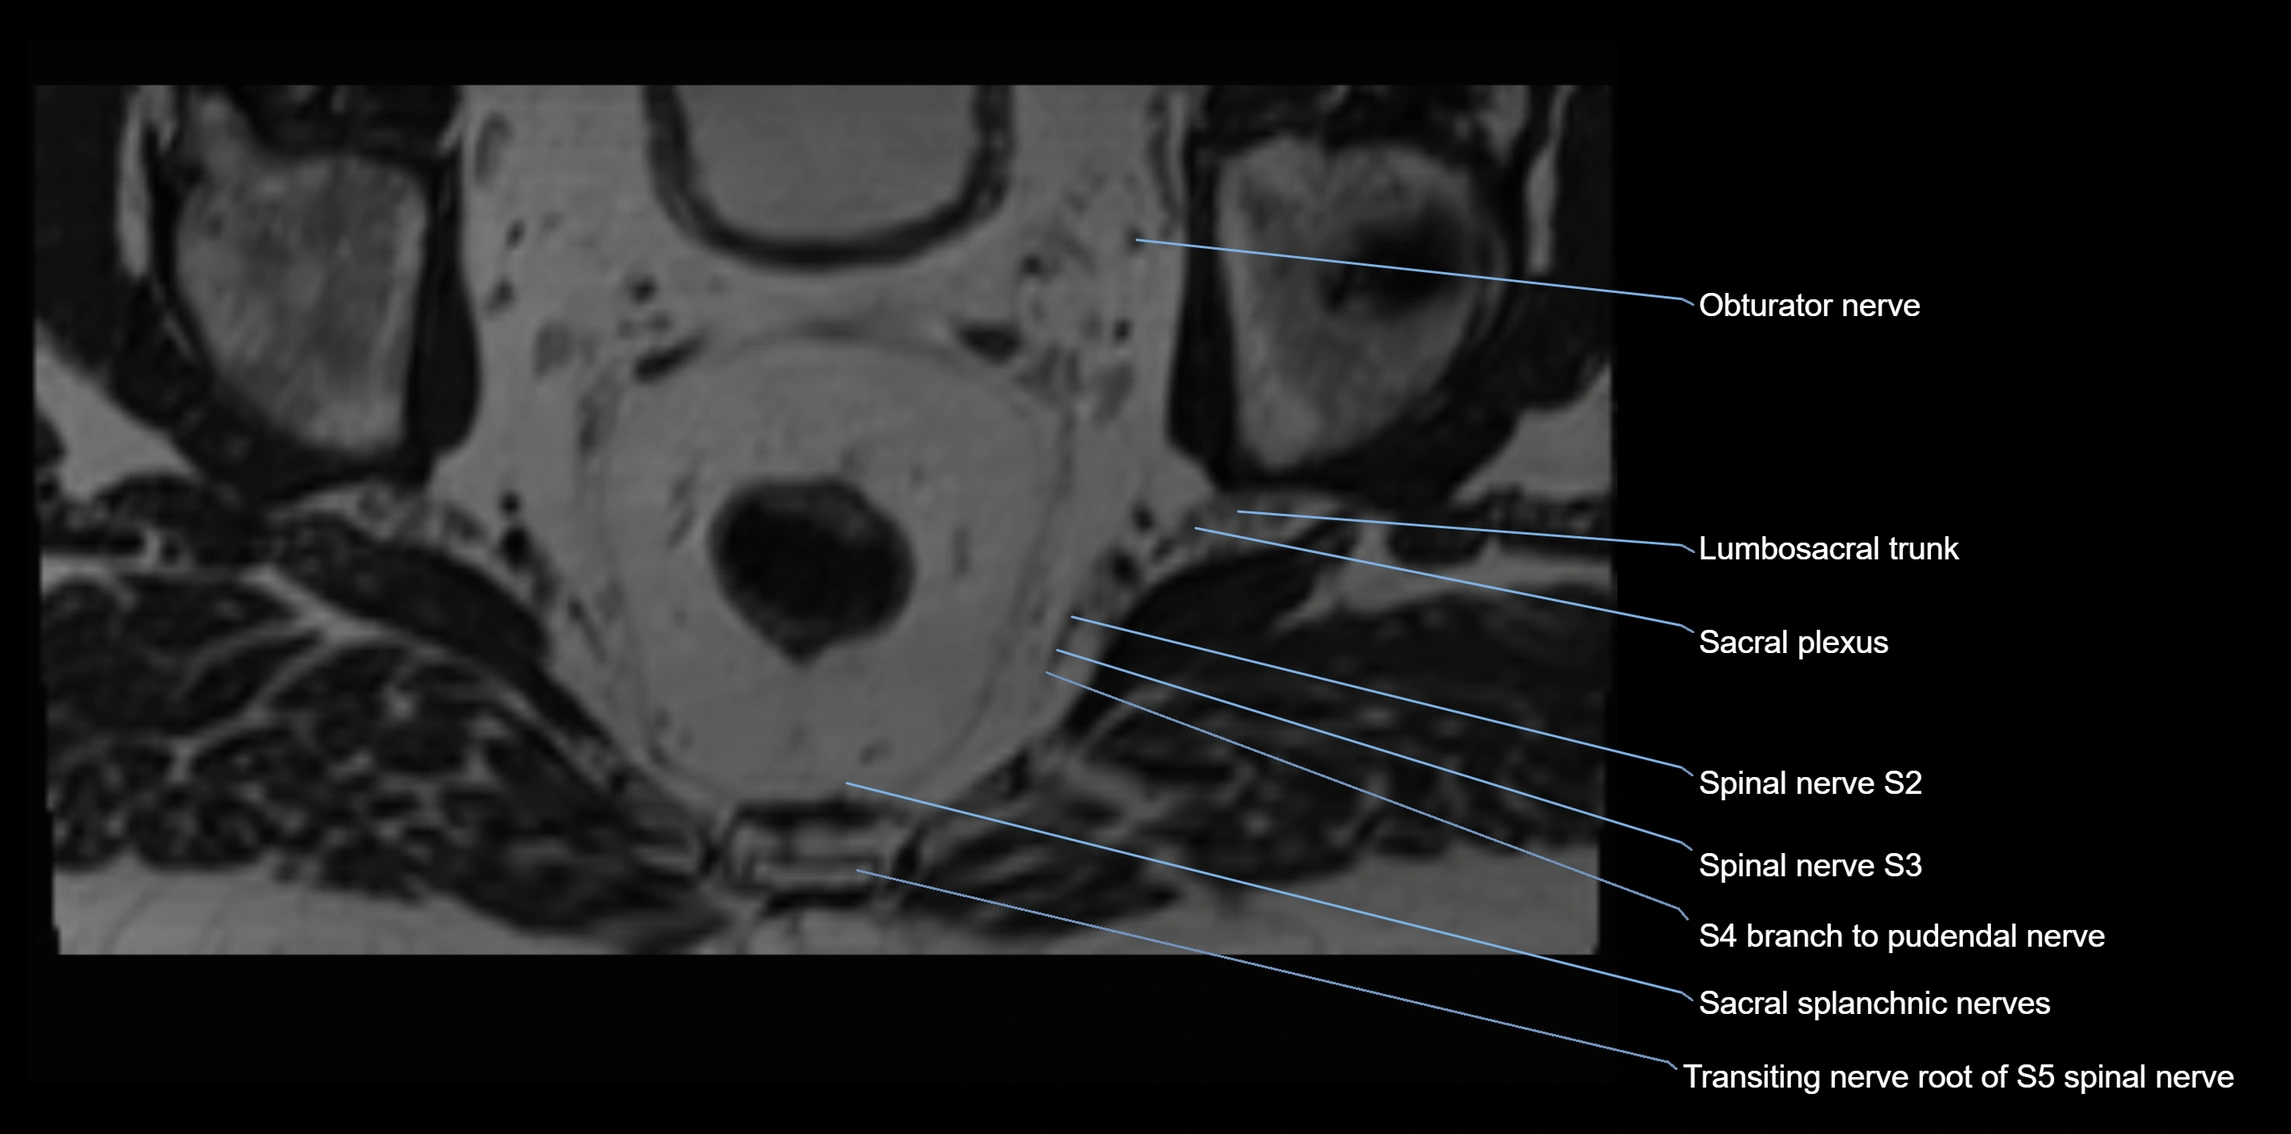

MRI Appearance

T1-weighted images:

• Nerve appears as a very thin low-to-intermediate signal intensity structure

• Surrounded by bright fat, aiding visualization

T2-weighted images:

• Nerve shows intermediate to mildly hyperintense signal compared to muscle

• Pathological involvement appears brighter

STIR (Short Tau Inversion Recovery):

• Normal nerve appears dark

• Inflamed or entrapped nerve appears bright hyperintense

T1 Fat-Sat Post-Contrast:

• Normal nerve enhances minimally

• Pathologic nerve (neuritis, entrapment, tumor infiltration) shows focal or diffuse enhancement

3D T2 SPACE / CISS:

• Nerve appears intermediate to mildly hyperintense compared to muscle

• Surrounded by bright fat or CSF, improving visualization

• Best sequence for mapping small pelvic nerves such as the anococcygeal